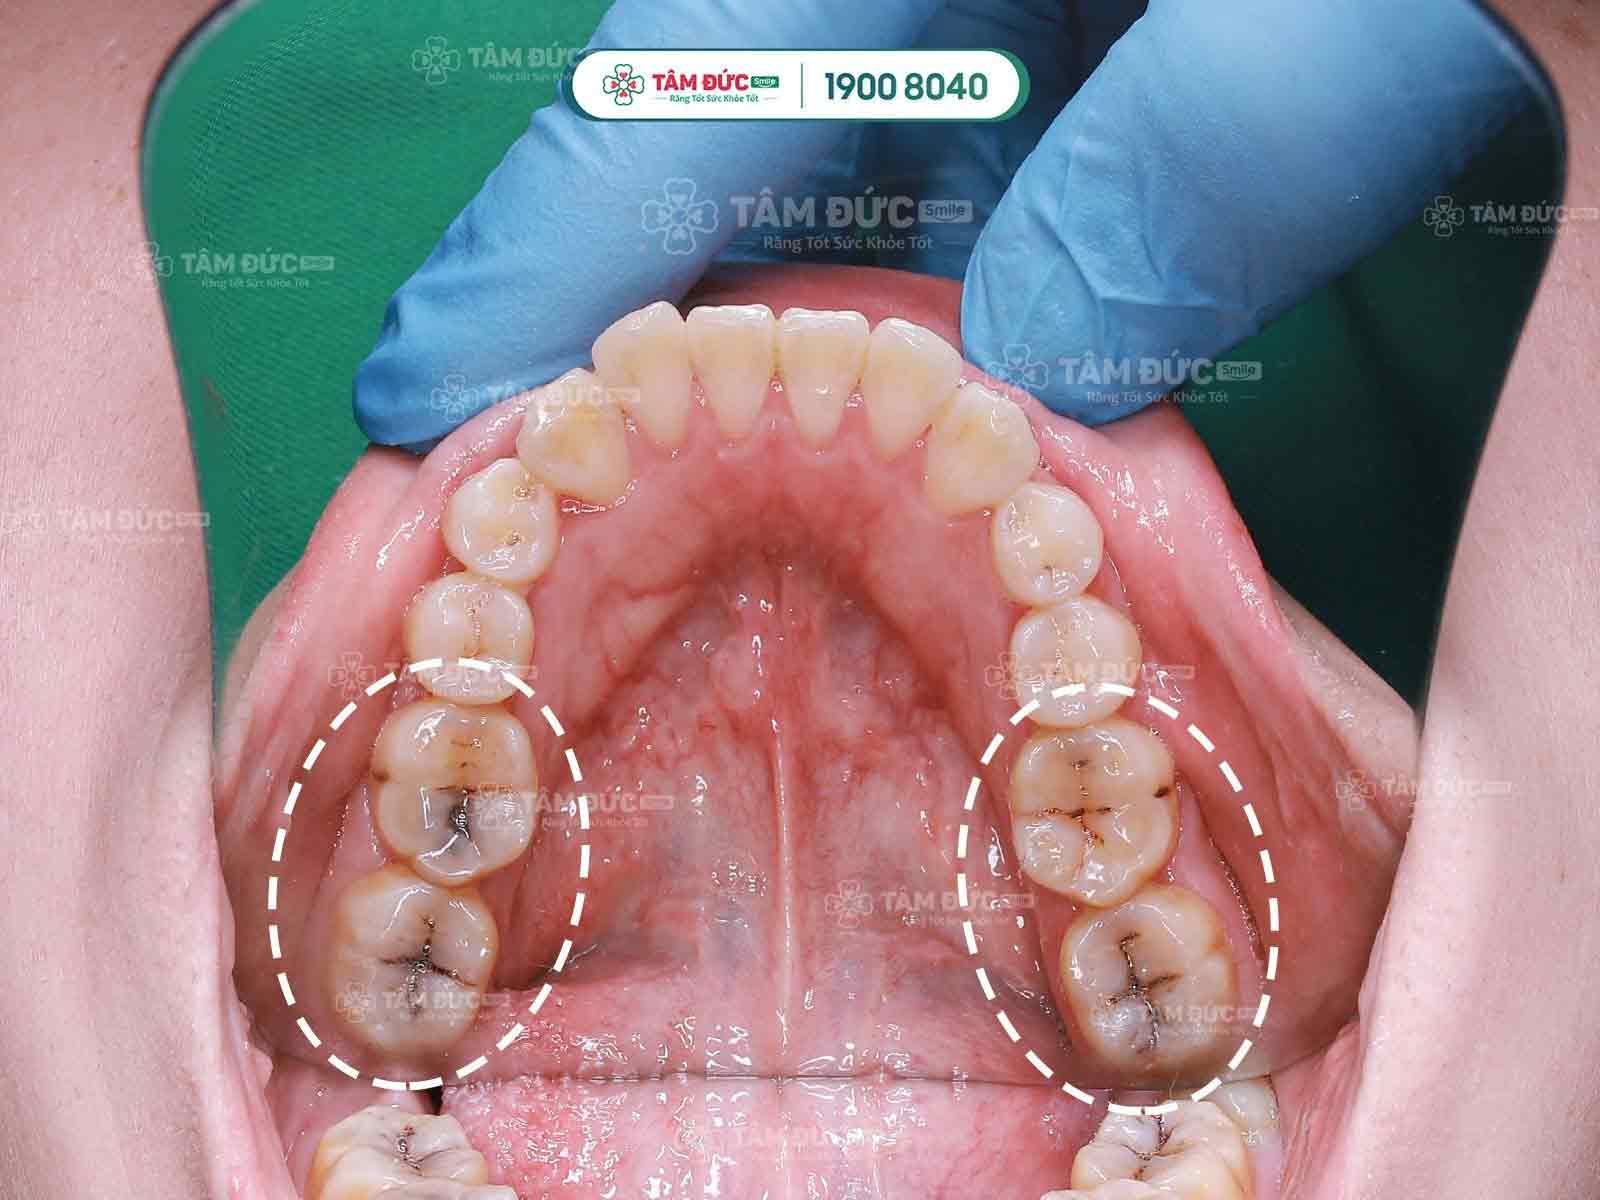

Khách hàng trám răng thẩm mỹ tại nha khoa Tâm Đức Smile